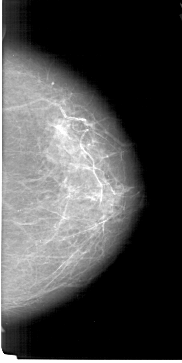

A_1190_1.LEFT_CC

LEFT_CC LINES 6466 PIXELS_PER_LINE 3451 BITS_PER_PIXEL 12 RESOLUTION 43.5 OVERLAY

FILE: A_1190_1.LEFT_CC.OVERLAY

TOTAL_ABNORMALITIES 1

ABNORMALITY 1

LESION_TYPE MASS SHAPE ROUND MARGINS ILL_DEFINED

ASSESSMENT 4

SUBTLETY 3

PATHOLOGY MALIGNANT

TOTAL_OUTLINES 1

BOUNDARY